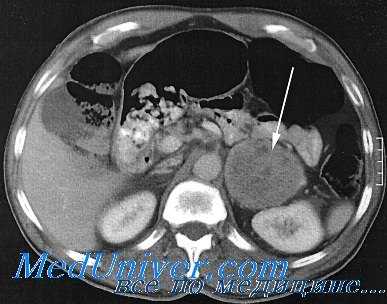

- Методы инструментальной диагностики. С целью топической диагностики феохромоцитомы выполняются УЗИ надпочечников и томография (КТ или МРТ) надпочечников, экскреторная урография, селективная артериография почечных и надпочечниковых артерий, сцинтиграфия надпочечников, рентгеноскопия или рентгенография органов грудной клетки (для исключения внутригрудного расположения опухоли). Изменения на ЭКГ неспецифичны, разнообразны и обычно носят временный характер, обнаруживаясь во время приступов.

Гормональную активность опухоли надпочечников можно оценить, используя селективную надпочечниковую флебографию – рентгенконтрастную катетеризацию надпочечниковых вен с последующим забором крови и определением в ней уровня гормонов. Исследование противопоказано при феохромоцитоме, т. к. может спровоцировать развитие криза. Размеры и локализацию опухоли надпочечников, наличие отдаленных метастазов оценивают по результатам УЗИ надпочечников, КТ или МРТ. Эти диагностические методы позволяют выявить опухоли- инциденталомы диаметром от 0,5 до 6 см.